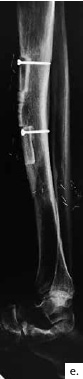

Ein 21-jähriger Motorradfahrer erlitt eine komplexe drittgradige Unterschenkelfraktur mit einem 9 cm langen proximalen Tibiadefekt und großer Integumentwunde (Abb. 4a). Aufgrund multipler Voroperationen bis zur Keimfreiheit nach stark verschmutzter Wunde und der erheblichen vaskulären Kompromittierung des Unterschenkels nach dem Unfall konnte ein vaskulärer Anschluss für die Defektdeckung nur über eine intraoperativ angelegte temporäre AV-Schlinge an die Femoralisgefäße im Adduktorenkanal erfolgen (Abb. 4b). Nach Auftrennen dieser Schlinge in einen venösen und einen arteriellen Schenkel konnte ein lateraler Oberschenkellappen („anterolateral thigh“; ALT) mikrovaskulär angeschlossen werden. An das distale Ende des R. descendens der A. circumflexa femoris lateralis an ein versorgendes Gefäß des ALT-Lappens wurde eine segmentierte freie osteofasziokutane Fibula (Abb. 4c) angeschlossen und im Double-Strut-Prinzip in den knöchernen Defekt eingesetzt (Abb. 4d u. e). Eine Wundheilungsstörung im kraniolateralen Bereich wurde durch ein drittes freies Transplantat (Paraskapularlappen) bedeckt (Abb. 4f u. g). Der Anschluss erfolgte an die Poplitealgefäße. Der nachfolgende Heilungsverlauf war ungestört. Eine individualisierte Kompressionsbestrumpfung fand für sechs Monate statt.